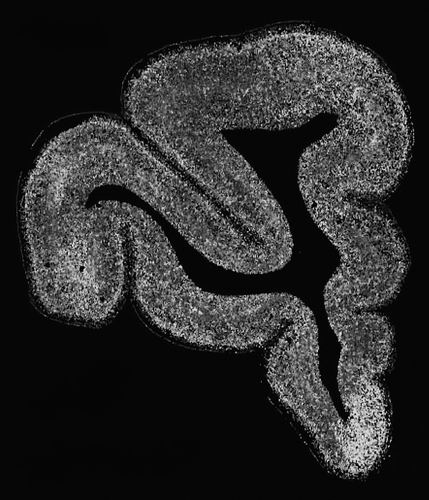

与抑郁症相关神经细胞在食蟹猴内侧前额叶皮层深部的分布。

在研究精神分裂症、抑郁症等复杂脑疾病及智商等性状时,团队借助gsMap探索了不同脑区与精神疾病及认知功能相关的细胞。他们发现,谷氨酸能神经元在多种脑疾病和性状中关联显著。结合药物数据库,他们发现内侧前额叶深部的高表达基因在精神药物靶点基因中的富集程度是其他大脑皮层区域的16倍,凸显了该脑区对抑郁症干预和靶向治疗的关键作用。